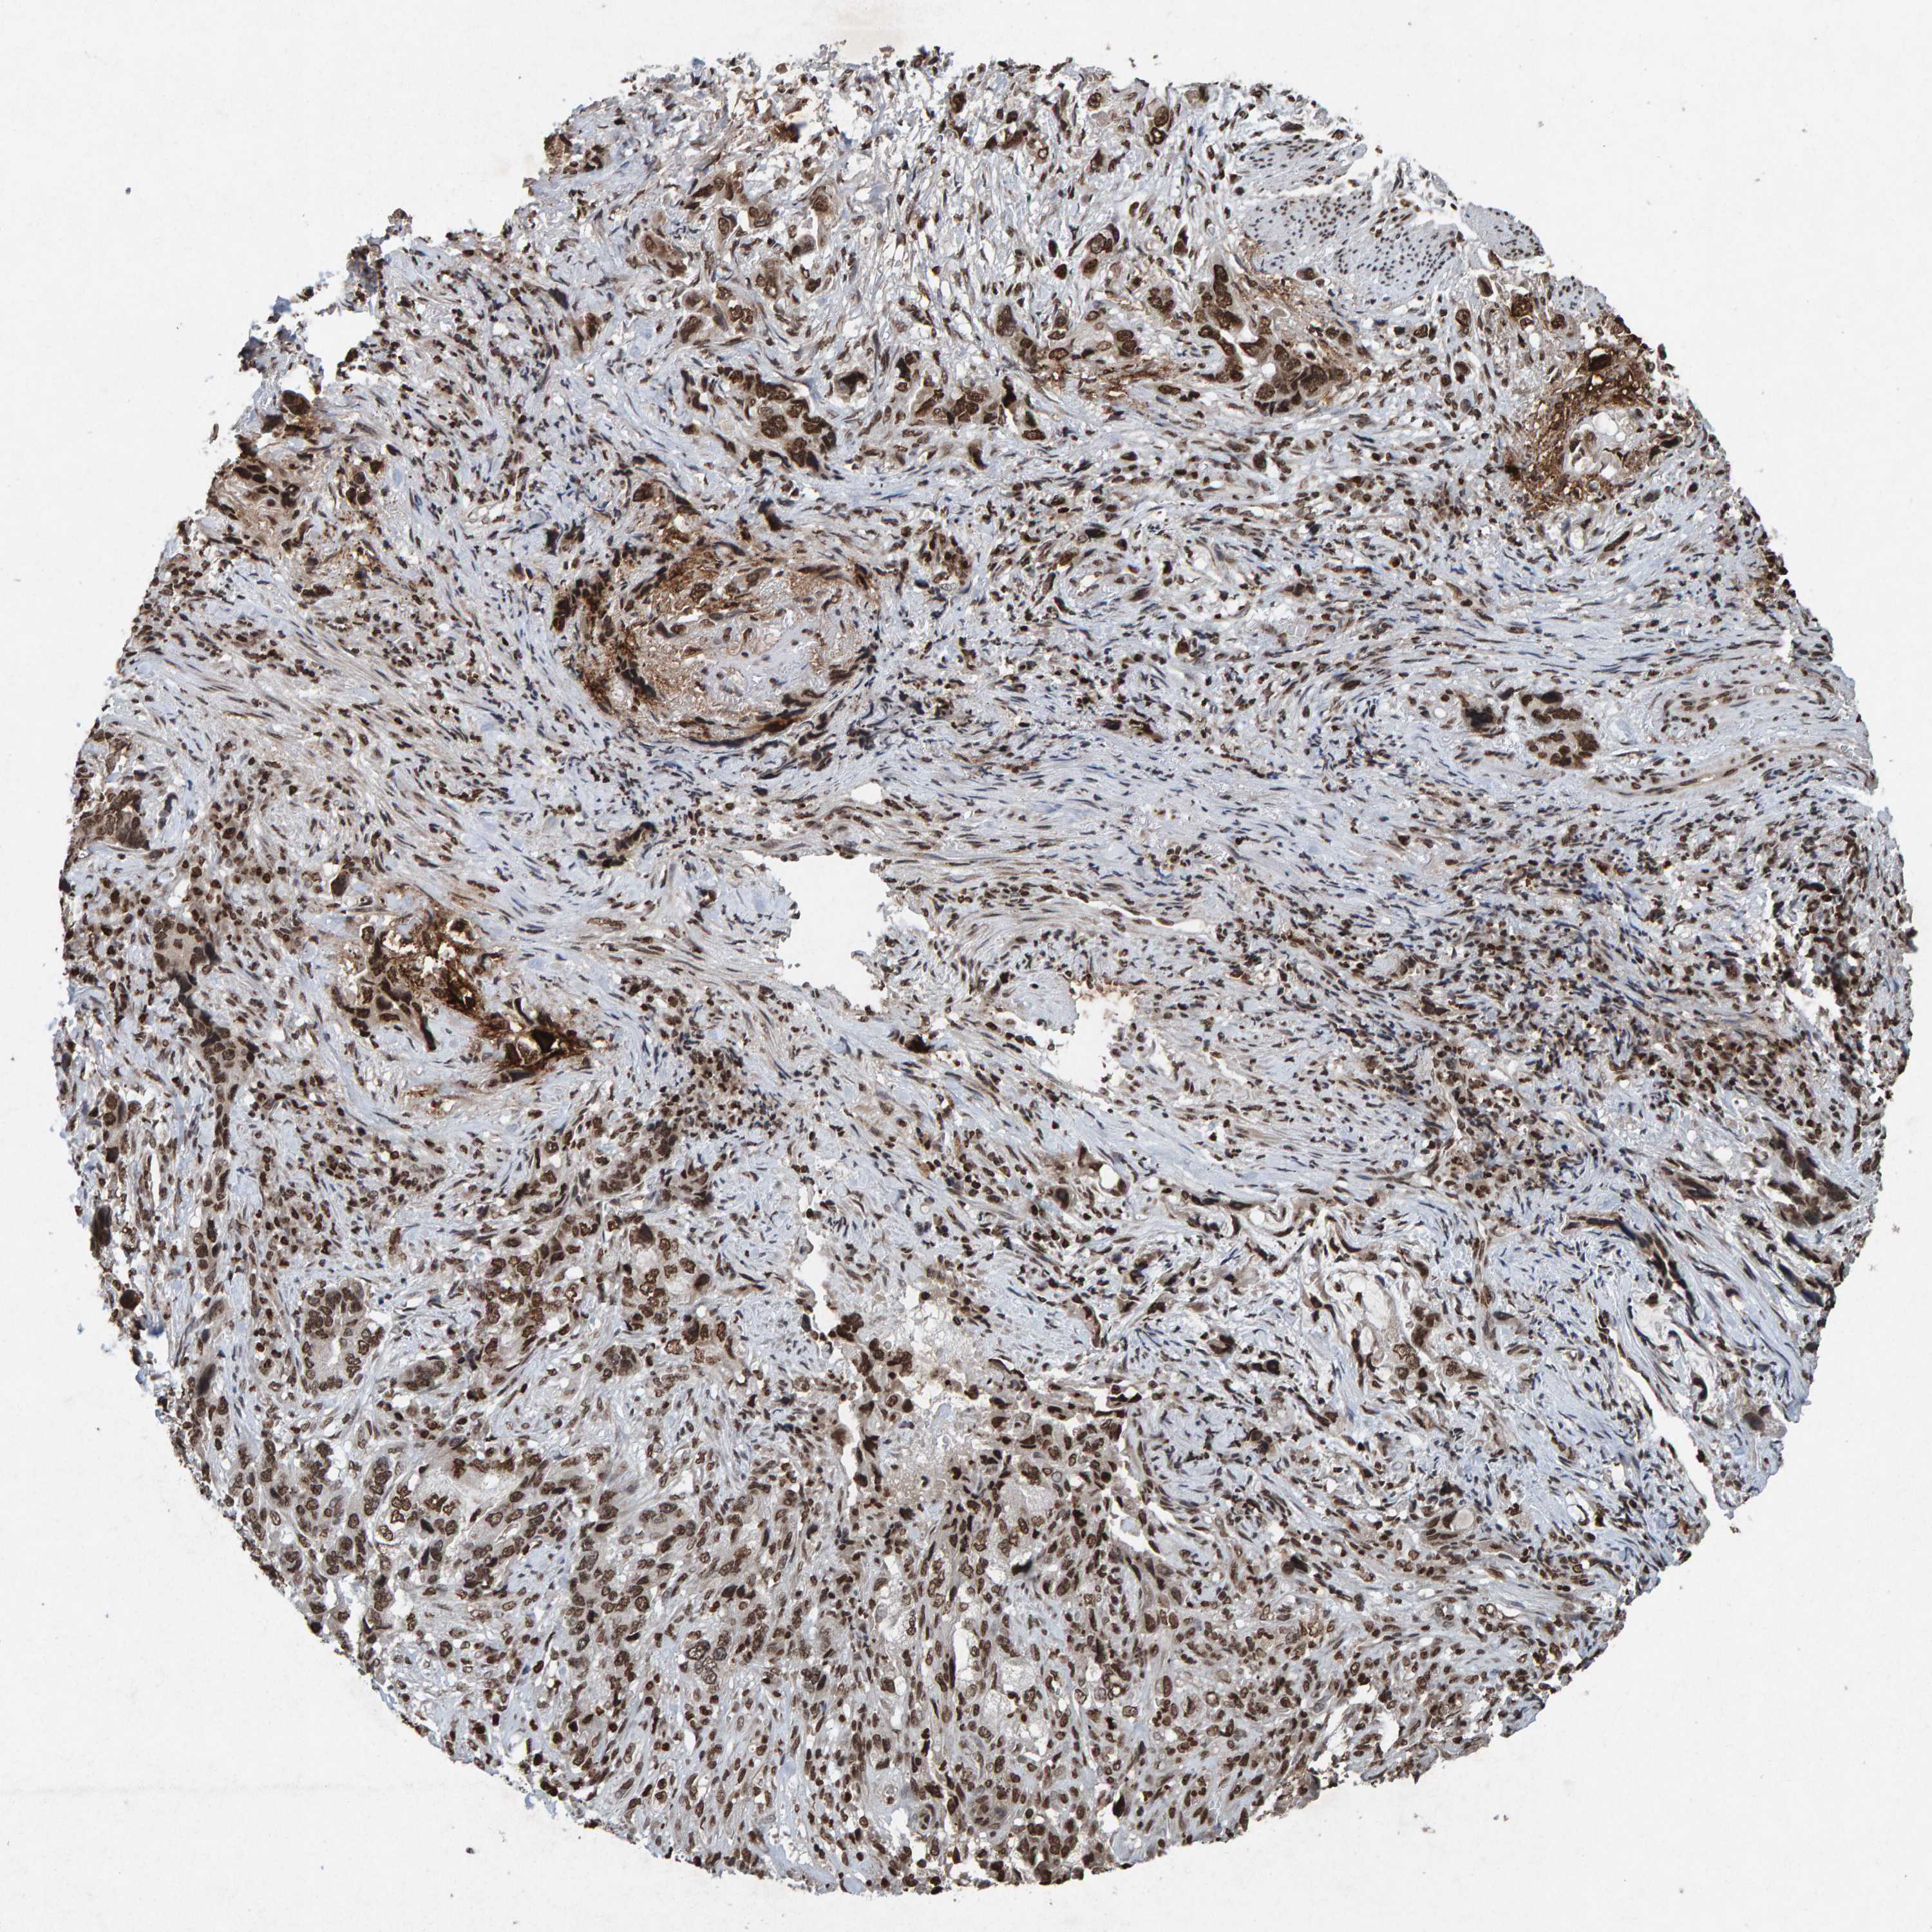

STOMACH CANCER - Protein expressioni

A mouse-over function shows sample information and annotation data. Click on an image to view it in a full screen mode. Samples can be filtered based on level of antibody staining by selecting one or several of the following categories: high, medium, low and not detected. The assay and annotation is described here.

Note that samples used for immunohistochemistry by the Human Protein Atlas do not correspond to samples in the TCGA dataset.

Antibody stainingi

Antibody staining in the annotated cell types in the current human tissue is reported as not detected, low, medium, or high, based on conventional immunohistochemistry profiling in selected tissues. This score is based on the combination of the staining intensity and fraction of stained cells.

Each image is clickable and will lead to virtual microscopy that enables deeper exploration of all samples and also displays staining intensity scores, fraction scores and subcellular localization as well as patient and tissue information for each sample.

Antibody HPA057236

Antibody CAB022549

Staining

High

Medium

Low

Not detected

Intensity

Strong

Moderate

Weak

Negative

Quantity

>75%

75%-25%

<25%

None

Location

Nuclear

Cytoplasmic/membranous

Cytoplasmic/membranous,nuclear

Adenocarcinoma, NOS

Adenocarcinoma, High grade